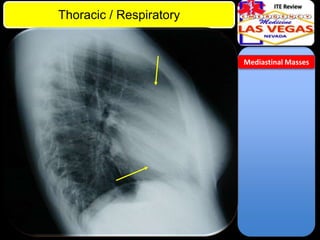

• Mediastinum divided into anterior,

middle, posterior compartments

• Anterior: from sternum to anterior

pericardium

• Mass in anterior mediastinum: five

“T”s

– Thymoma (consider myasthenia

gravis)

– Thyroid (retrosternal)

– Teratoma (teeth, hair, etc.)

– T cell lymphoma

– "Terrible“ (carcinoma)

Mediastinal Masses